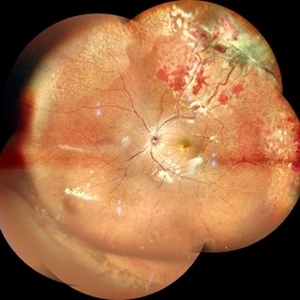

RPE rip in a case of Idiopathic polypoidal choroidopathy RPE rip in a case of Idiopathic polypoidal choroidopathyOct 23 2022 by Anjana Mirajkar, MS Ophthalmology Color photo wide field image in a of 61 year old male with RPE rip in a case of Idiopathic Polypoidal Choroidopathy. Photographer: Dr. Anjana Mirajkar -Retina Foundation, Ahmedabad Condition/keywords: RPE Rip